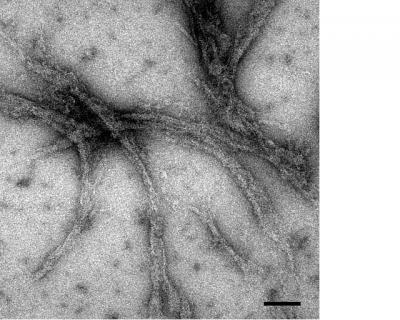

"We were surprised to discover that both genetically defected as well as normal, or wild-type (WT), myocilin are readily triggered to produce very stable fibrous residue containing a pathogenic material called amyloid," said Lieberman, whose work was published in the most recent Journal of Molecular Biology .

Amyloid formation, in which a protein is converted from its normal form into fibers, is recognized as a major contributor to numerous non-ocular disorders, including Alzheimer's, certain forms of diabetes and Mad Cow disease (in cattle). Scientists are currently studying ways to destroy amyloid fibrils as an option for treating these diseases. Further research, based on Lieberman's findings, could potentially result in drugs that prevent or stop myocilin amyloid formation or destroy existing fibrils in glaucoma patients.

"The amyloid-containing myocilin deposits we discovered kill cells that maintain the integrity of TM tissue," said Lieberman. "In addition to debris from dead cells, the fibrils themselves may also form an obstruction in the TM tissue. Together, these mechanisms may hasten the increase of intraocular pressure that impairs vision."